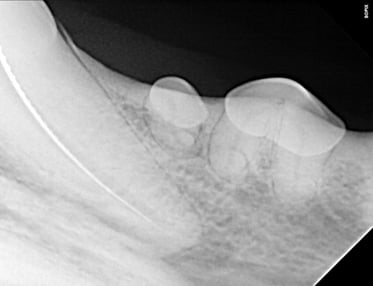

Below: Radiograph finding master file size to clean canal walls appropriately and find master cone size of gutta percha - note how spade of light speed file fills entire apex

%20Case%202%20-%20July%202024/Master%20file%20during%20RCT%20.jpg?width=373&height=287&name=Master%20file%20during%20RCT%20.jpg)

Cleaning and shaping of the canal were meticulously carried out using Dentsply NiTi and LightSpeed files, alternating with suction-assisted sterile saline and sodium hypochlorite solutions to maintain optimal cleanliness.